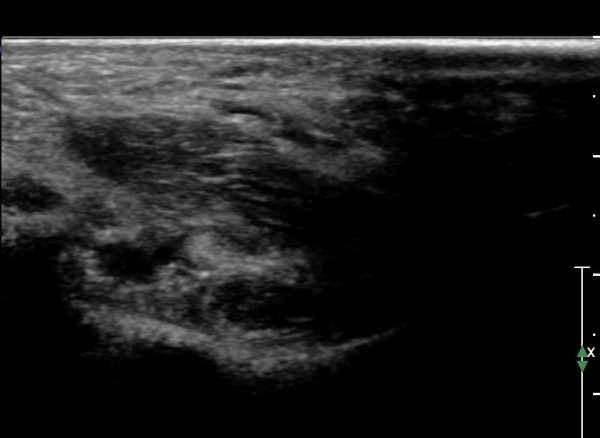

Å½ÃËÁö¸¦ Á¶±Ý ´õ ¸»´ÜÀ¸·Î À̵¿ÇÏ¿© sustentaculum  tali À§Ä¡¿¡ ¿À´Ï À幫Áö±¼±Ù°Ç ÁÖº¯¿¡ ¼ö¾×Àú·ù°¡

°üÂûµÇ°í ³»Ãø Á·Àú½Å°æÀÇ ÀüÀ§°¡ °üÂûµÊ. sustentaculum  tali Ç¥Ãþ¿¡ À§Ä¡ÇÑ ÀåÁ·Áö±¼±Ù°ÇÀº

ºñµî¹æ¼º(anisotropic) ÀΰøÀ½¿µ(artifact)¿¡ ÀÇÇÏ Àú¿¡ÄÚ µ¢¾î¸®·Î °üÂûµÊ(»çÁø 3).